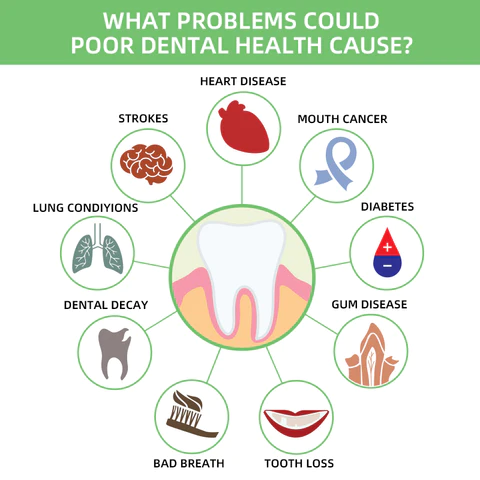

What Problems Could Poor Dental Health Cause?

- Oral diseases, while largely preventable, pose a major health burden for many countries and affect people throughout their lifetime, causing pain, discomfort, disfigurement, and even death.

- It is estimated that oral diseases affect nearly 3.5 billion people.

- Untreated dental caries (tooth decay) in permanent teeth is the most common health condition according to the Global Burden of Disease 2019.

- Treatment for oral health conditions is expensive and usually not part of universal health coverage (UHC).

- Most low- and middle-income countries do not have sufficient services available to prevent and treat oral health conditions.

- Oral diseases are caused by a range of modifiable risk factors common to many noncommunicable diseases (NCDs), including sugar consumption, tobacco use, alcohol use poor hygiene, and their underlying social and commercial determinants.